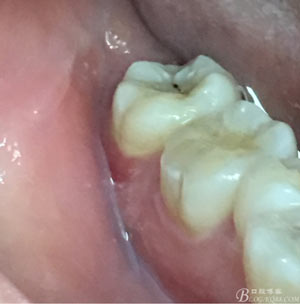

患者、申xx、女、40歲,主訴:左側(cè)下頜后牙牙齦紅腫不適數(shù)月。??茩z查:37合面有一開(kāi)髓孔。髓腔內(nèi)有一暫封小棉球,探針?biāo)枨坏撞砍鲅蔀樵谕庠褐委煂?dǎo)致底穿。x線片檢查:37頰側(cè)齦下有一枚多生牙,多生牙壓迫頰側(cè)牙根及牙體組織大量吸收。

圖2.37牙冠基本完好,松動(dòng)Ⅰ度。合面有一開(kāi)髓孔被棉球覆蓋,頰側(cè)牙齦輕度紅腫。